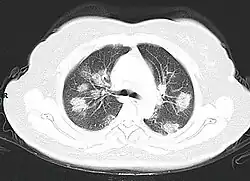

A CT scan of a person with COVID-19 shows lesions (bright regions) in the lungs

CT scan of rapid progression stage of COVID-19

Chest CT scans may be helpful to diagnose COVID‑19 in individuals with a high clinical suspicion of infection but are not recommended for routine screening.[175][187] Bilateral multilobar ground-glass opacities with a peripheral, asymmetric, and posterior distribution are common in early infection.[175][188] Subpleural dominance, crazy paving (lobular septal thickening with variable alveolar filling), and consolidation may appear as the disease progresses.[175][189] Characteristic imaging features on chest radiographs and computed tomography (CT) of people who are symptomatic include asymmetric peripheral ground-glass opacities without pleural effusions.[190]

Many groups have created COVID‑19 datasets that include imagery such as the Italian Radiological Society which has compiled an international online database of imaging findings for confirmed cases.[191] Due to overlap with other infections such as adenovirus, imaging without confirmation by rRT-PCR is of limited specificity in identifying COVID‑19.[190] A large study in China compared chest CT results to PCR and demonstrated that though imaging is less specific for the infection, it is faster and more sensitive.[174]